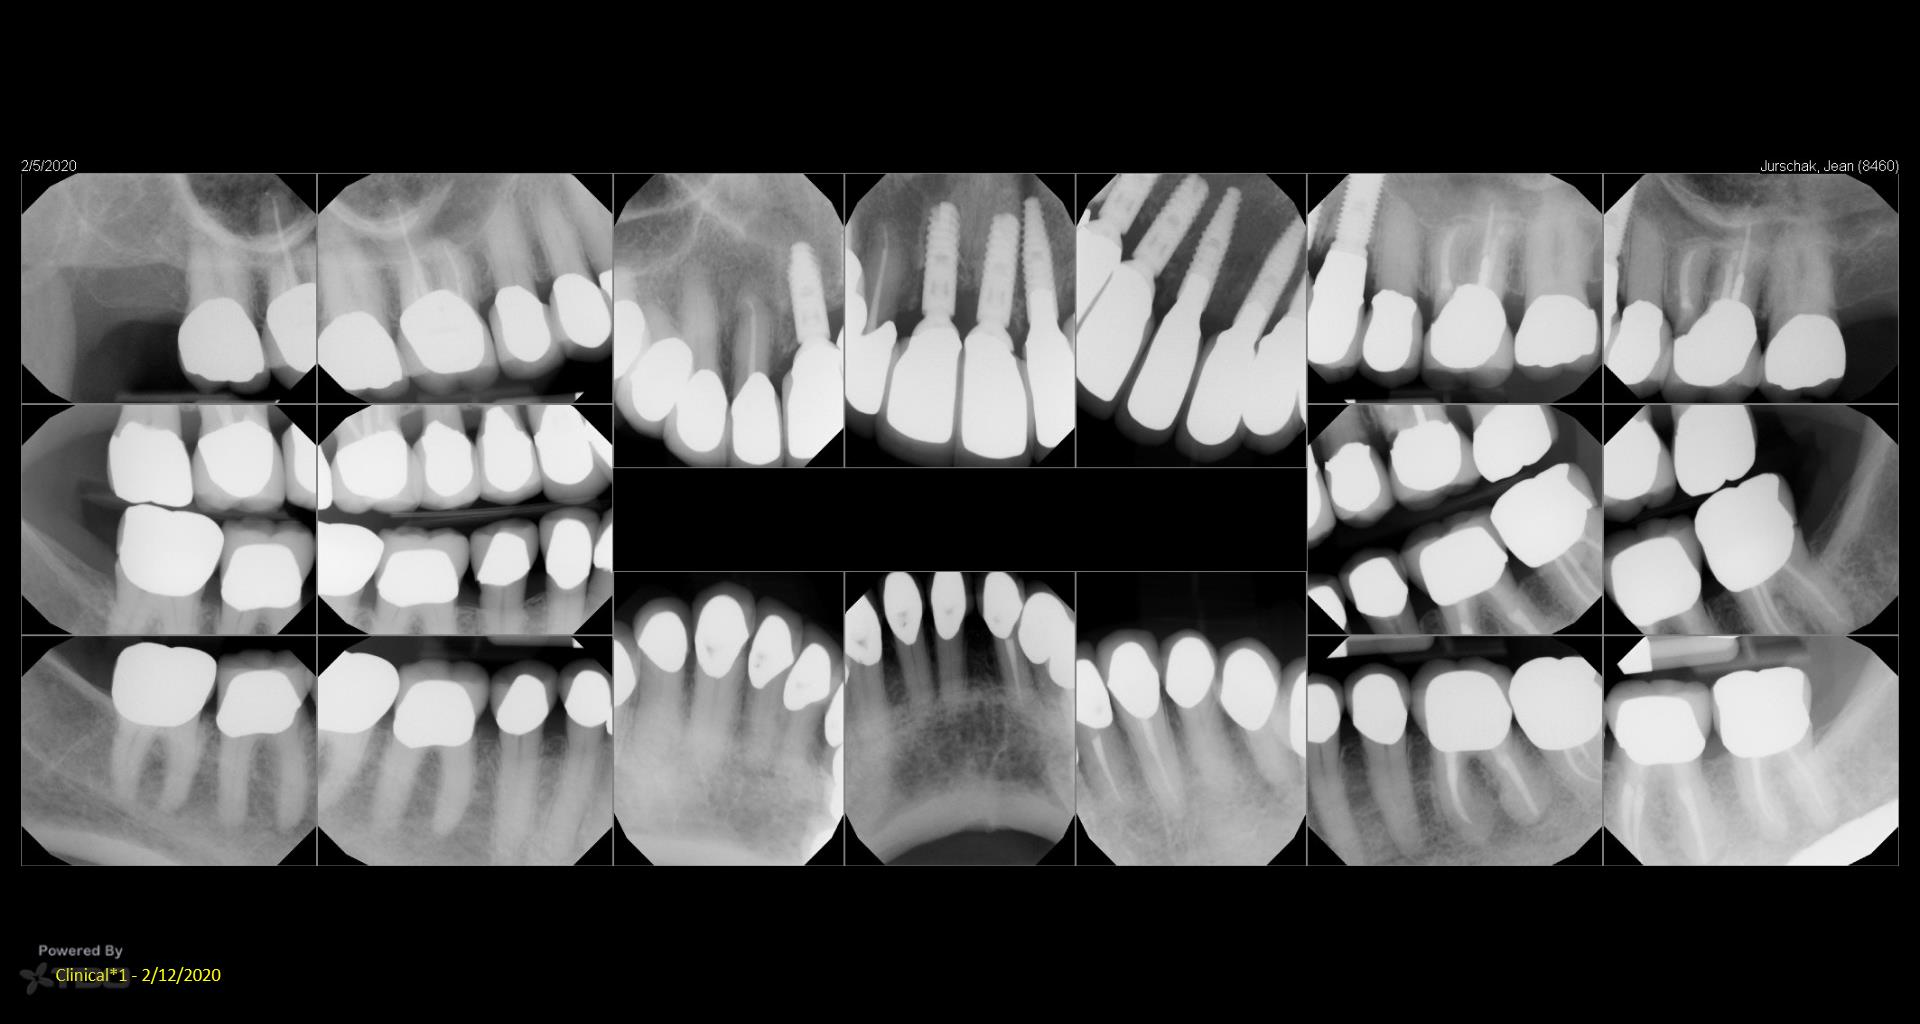

I did a retreat #19 15 years ago. Today symptom free but #18 looks suspicious and maybe even #19……. Perfect case for monitoring….not anxious to do another retreat… gbc

My experience with retreat #19 fifteen years ago was transformative, and I’m grateful to be symptom-free today. However, I’ve noticed convalescent hospital some concerning signs with #18 and possibly #19, which makes me cautious. While I appreciate the value of retreats, I’m not eager to dive back in just yet. Monitoring feels essential now.